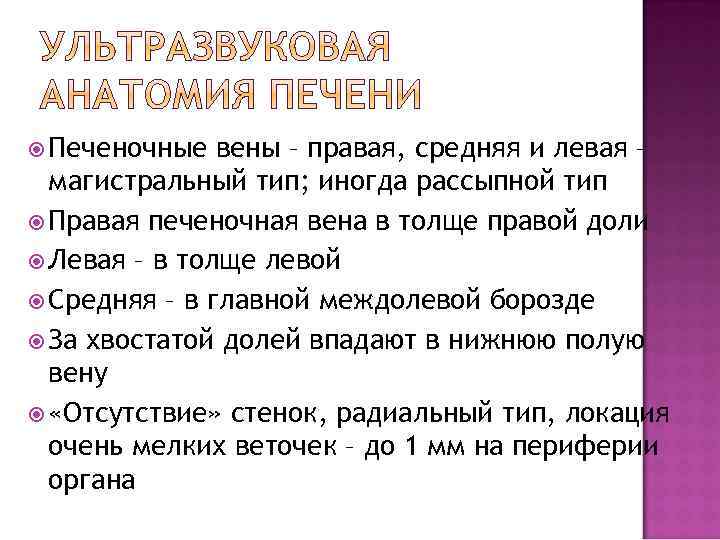

Печеночные вены – правая, средняя и левая – магистральный тип; иногда рассыпной тип Правая печеночная вена в толще правой доли Левая – в толще левой Средняя – в главной междолевой борозде За хвостатой долей впадают в нижнюю полую вену «Отсутствие» стенок, радиальный тип, локация очень мелких веточек – до 1 мм на периферии органа